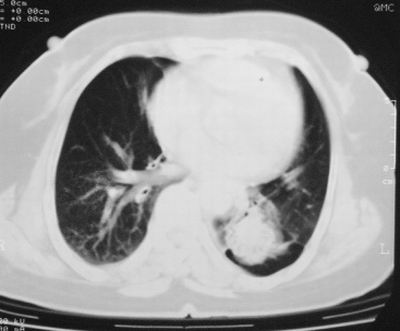

左下肺软组织块影,有分叶、毛刺、空泡及胸膜牵拉征,左下肺周围性肺癌。

左肺下叶周围型肺癌,支持!(软组织肿块+分叶+毛刺+空泡+胸膜凹陷征)

左下肺软组织密度影,可见分叶,边缘可见毛刺征,胸膜增厚,强烈要求左下肺周围型肺癌

我考虑炎性假瘤:1,边界模糊.2,邻近胸膜增厚,胸膜外脂肪也增厚.3,周围有肺气肿征.4,无胸水,无淋巴结肿大.